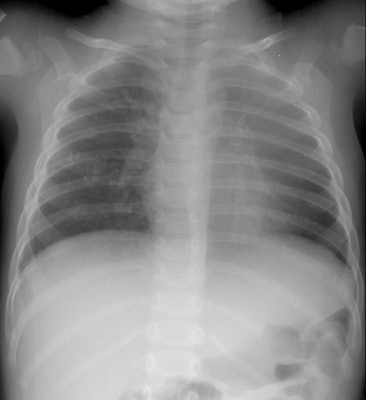

Left upper lobe collapse

The patient below presented with a history of reactive airways disease and shortness of breath. The frontal CXR demonstrated a vague opacity in the left upper lung that obscured the left upper mediastinal border and a segment of the left heart border. Note that the lateral edge of the opacity is ill-defined. The left hila was slightly uplifted. Lateral CXR demonstrated a retrosternal density (black arrows) representing the collapsed left upper lobe displaced anteriorly. |